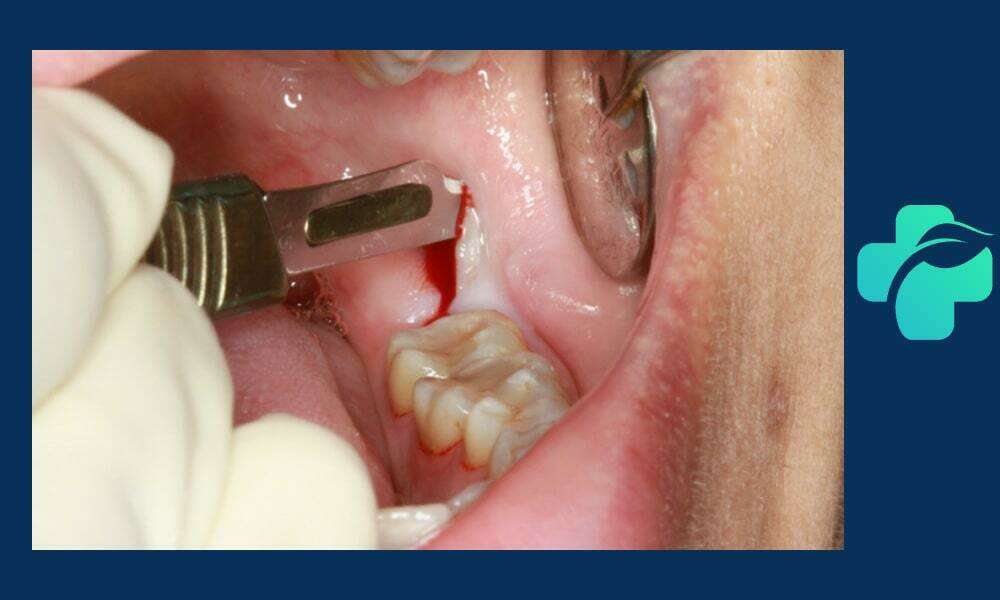

جراحی دندان عقل نهفته زمانی انجام می شود که دندان داخل لثه گیر کرده و رشد کامل نداشته باشد. در این حالت، دندانپزشک نیاز دارد تا برش لثه ایجاد کرده و در برخی موارد استخوان اطراف دندان را بردارد تا دسترسی به دندان فراهم شود. این نوع جراحی طولانی تر و پیچیده تر از جراحی ساده است و ممکن است با تورم و ناراحتی بیشتری همراه باشد. مراقبت دقیق بعد از جراحی، شامل استفاده از مسکن، رعایت رژیم غذایی نرم و جلوگیری از فشار روی ناحیه جراحی، برای جلوگیری از عفونت و تسریع بهبودی ضروری است. جراحی دندان عقل نهفته اغلب برای پیشگیری از عفونت، درد یا آسیب به دندان های مجاور توصیه می شود.

- نیاز به برش لثه

- ممکن است نیاز به برداشت استخوان اطراف دندان باشد

- زمان جراحی متوسط

- تورم و درد بیشتر نسبت به جراحی ساده

- مراقبت دقیق پس از جراحی ضروری